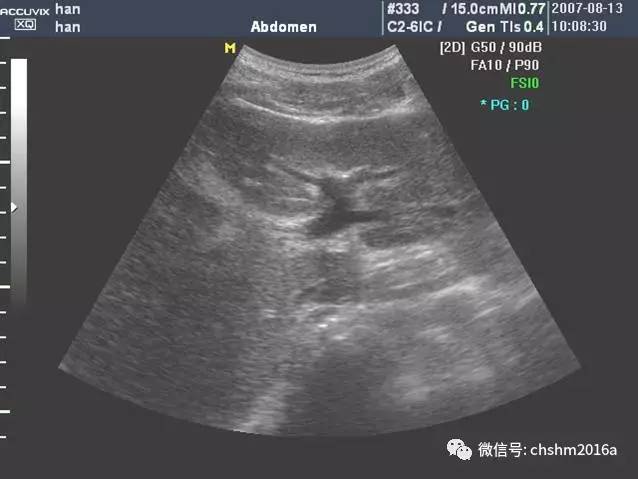

肝左内外叶的超声分界(肝圆韧带-门静脉左支矢状部-静脉韧带)